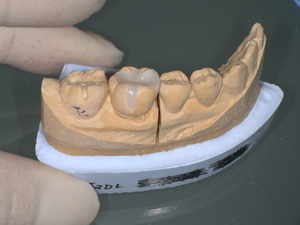

2. 精密な型取り

患者様の顔立ちや周囲の歯に完璧に調和する形状を作るため、 精密な型取り を実施。自然な咬み合わせと審美性を両立させます。

3. ジルコニアセラミッククラウンの作製

最新技術を用いて、 透明感と耐久性を両立した被せ物 を作製。